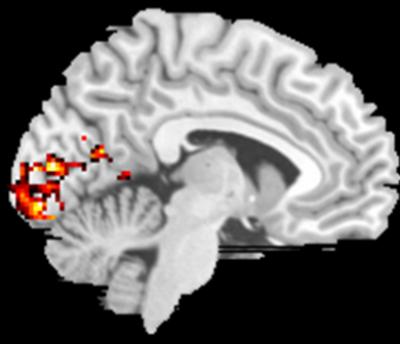

The researchers presented 13 volunteers with a series of tests designed to visually stimulate their peripheral regions and measure brain activity with functional magnetic resonance imaging. They found that when patients visually stimulated the preferred retinal locations, they increased brain activity in the same parts of the visual cortex that are normally activated when healthy patients focused on objects in their central visual field. They concluded that the brain had reorganized itself.

The parts of the visual cortex that process information from the central visual field in patients with normal vision were reprogrammed to process information from other parts of the eye, parts that macular degeneration patients use instead of their central visual areas.